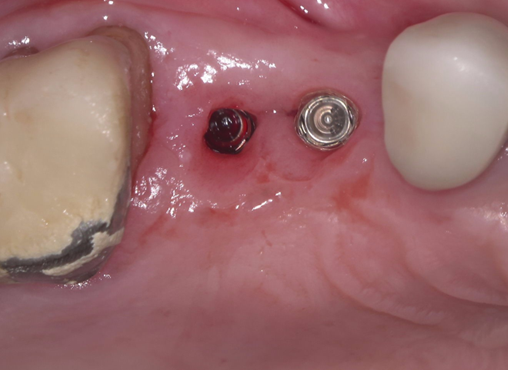

①歯槽頂よりサイナス

リフトを行いました。

②血液成分とカルシウム材料により骨造成をしました。

③ガイデッドサージェリーにてインプラント埋入しました。

④計画通りの埋入が出来ました。